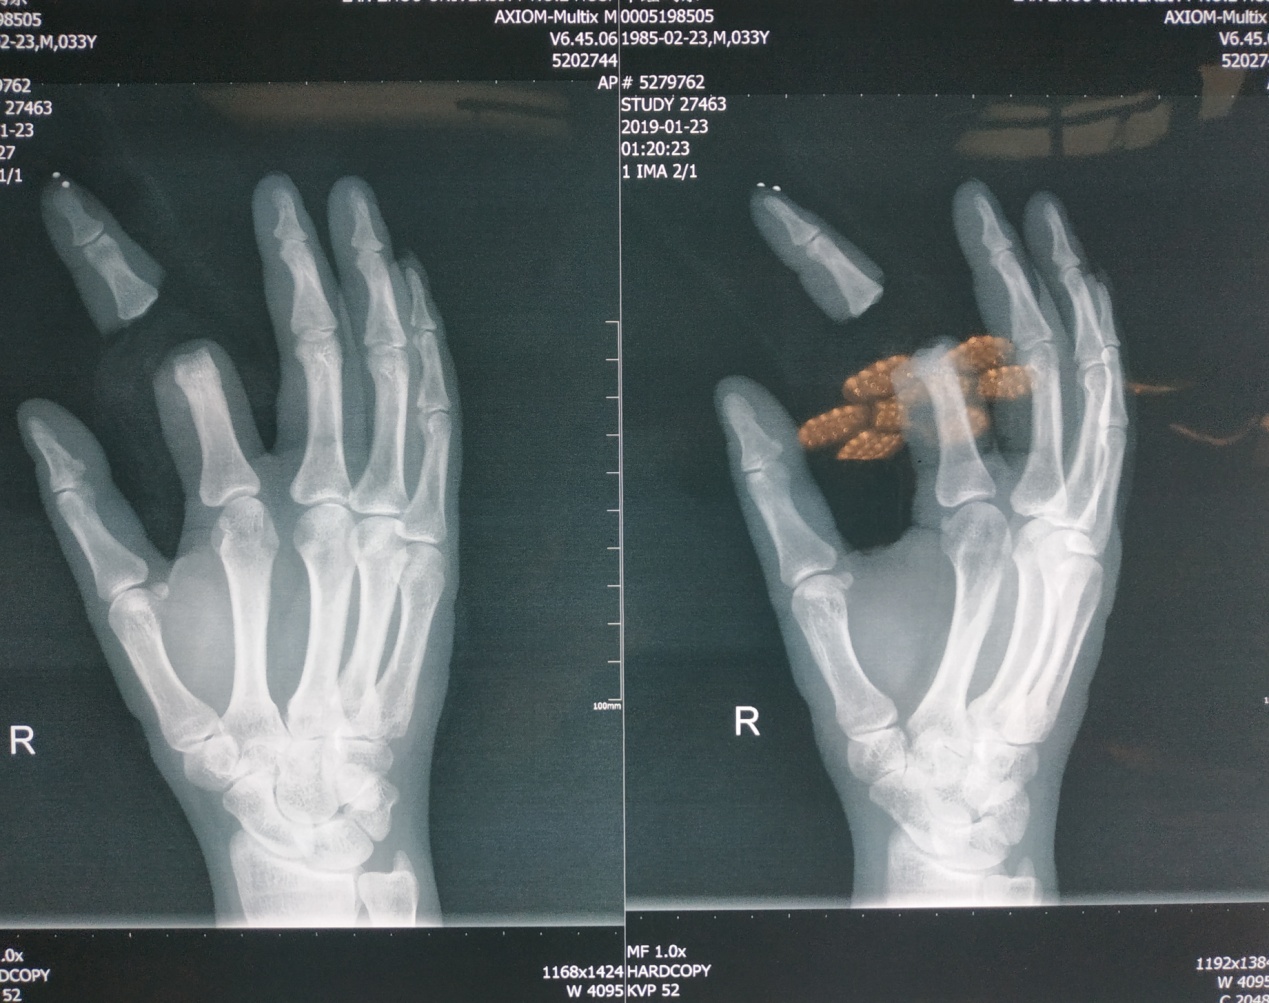

“没想到我的手指还能活”1月23日零点36分,33岁的牛女士,因外伤致右手食指近侧指间关节离断5小时后,就诊于我院急诊外科。经过充分、迅速的术前检查及评估后,牛女士在急诊手术室接受局部麻醉下行左手食指清创再植术。术后,患者恢复良好,于1月30日康复出院。